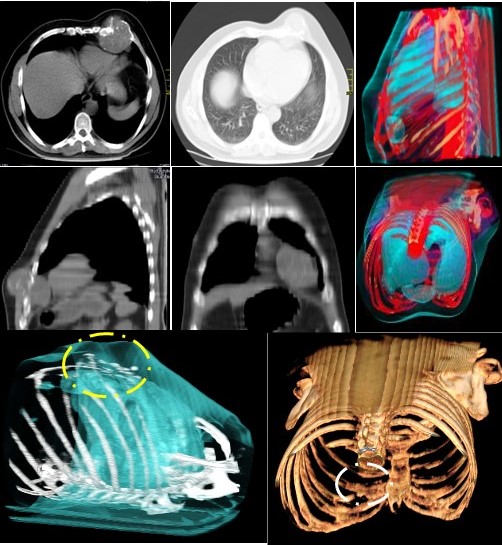

La radiografía simple mostró un defecto lítico bien definido, de 70 mm en la VII costilla izquierda. La TC de alta resolución demuestra un área de destrucción ósea lítica extensa, que mide 110 mm x 100 mm x 59 mm de diámetros transverso y anteroposterior, con destrucción de la cortical. Los márgenes estaban delineados con alguna matriz osificante (Figura 1). Sin evidencia de extensión al tejido blando adyacente. Con alta sospecha de una lesión ósea-cartilaginosa benigna, como un condroma.

En la mayoría de los pacientes del sexo masculino que tienen entre 10 y 25 años los condroblastomas protagonizan aproximadamente del 1 % al 2 % de todas las neoplasias óseas al momento de su diagnóstico. En nuestro caso, la edad en el momento del diagnóstico era 46 años, una edad muy exigua frecuente. Asimismo, no se perciben agentes de riesgo ni patogénesis del condroblastoma. Por lo general, el condroblastoma afecta un solo hueso, pero puede afectar dos partes anatómicas diferentes, suele ser una lesión bien circunscrita, redonda u ovalada en la radiografía simple. La TC puede mostrar mineralización de la matriz, erosión cortical y extensión de tejidos blandos como sucedió en nuestro caso. El dolor es el síntoma más común, generalmente presente durante menos de 1 año (15).